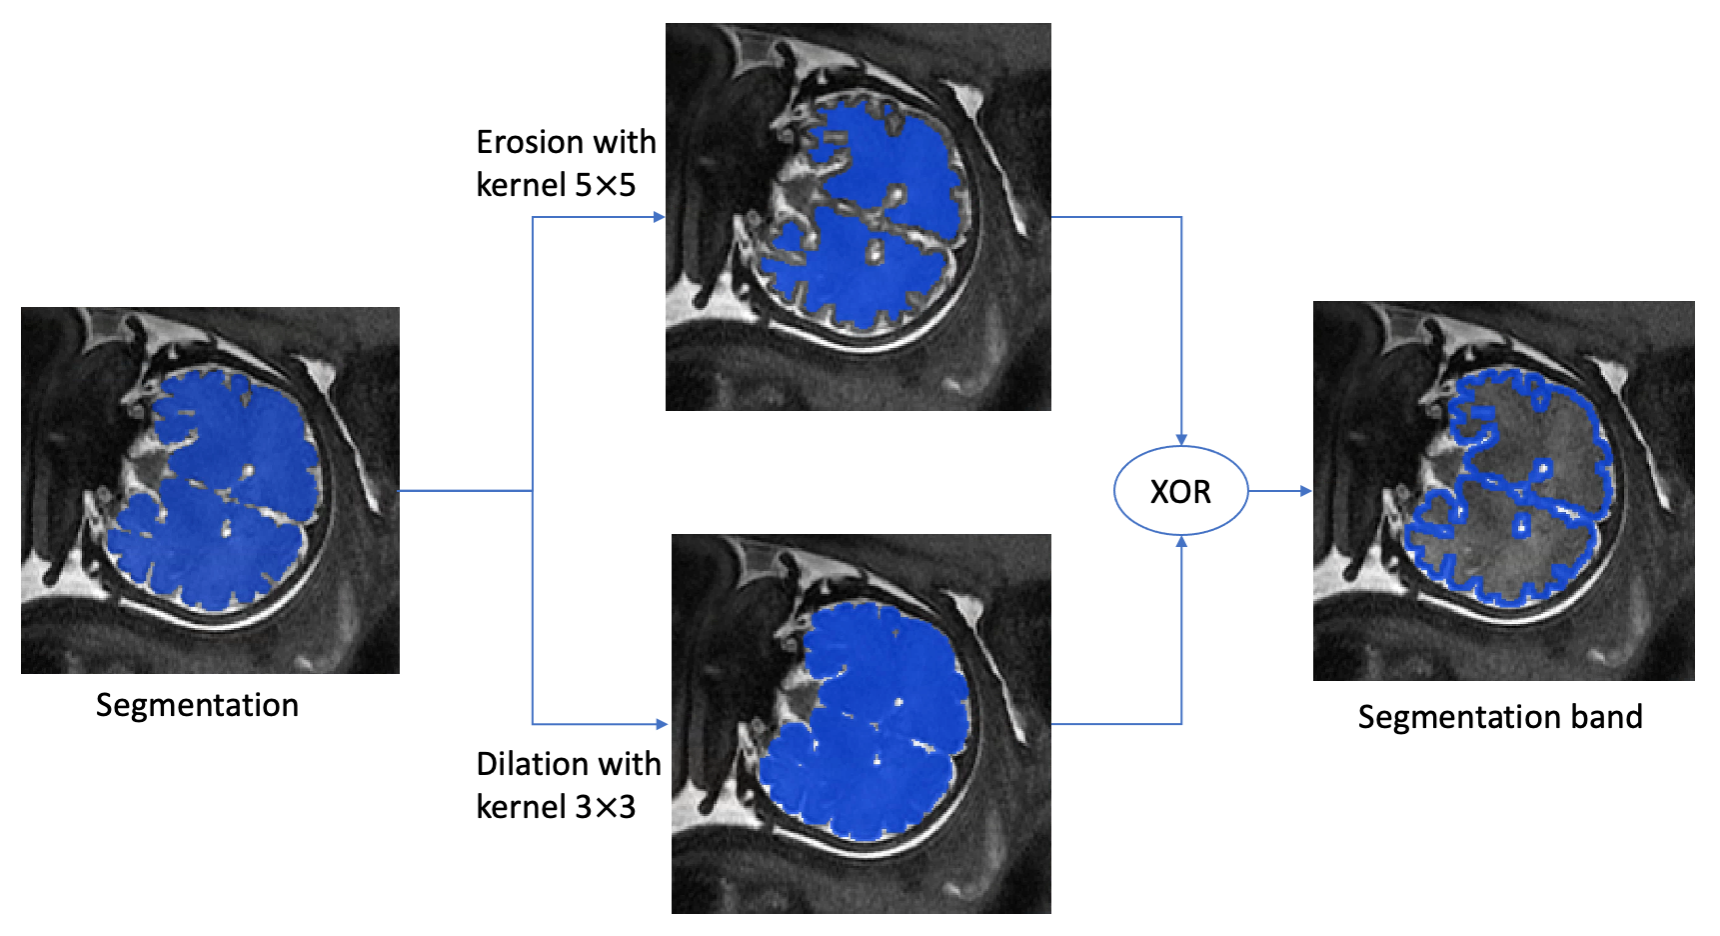

3.1 Contours and Bands Extraction

The segmentation contour and the band around it are computed as follows. First, binary thresholding is applied to the network output with a predefined threshold . Then, the contours of both the network result and the ground truth segmentation are extracted using erosion and XOR operations (Fig. 1). Finally, the bands are extracted using erosion, dilation and XOR operations (Fig. 3).